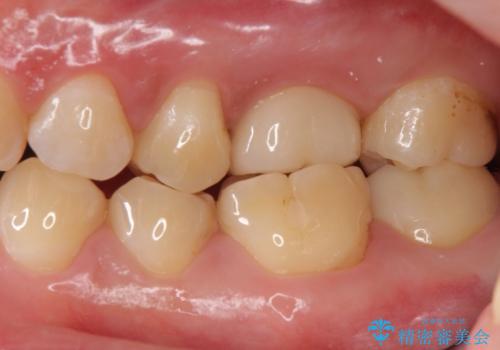

本来は歯茎をしっかりと下げる外科処置が適応となるケースでしたが、ご希望がなかったため最小限の侵襲に抑えて治療を行いました。

根の中を洗浄し、結果的に適合の良い被せ物をセットすることができました。